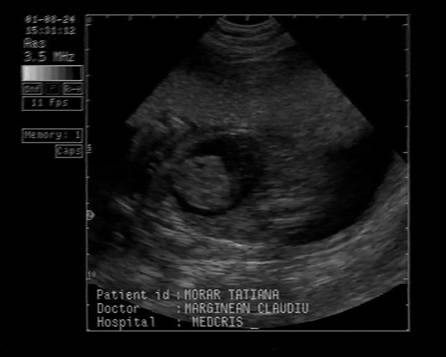

Fig . nr. 248. Chist de plex choroid , unilateral, la o sarcina de 17 sapt.

Fig. nr. 249. Hidrocefalie interna unilaterala aparuta la 28 sapt si cu evolutie rapida, postpartum se confirma suspiciunea de diagnostic: hemoragie cerebrala